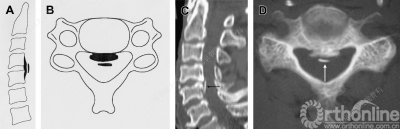

根据患者颈椎侧位片,可将OPLL分为以下四种类型:

A.连续型、B.混合型、C.节段型、D.局灶型

CT是诊断后纵韧带骨化的金标准,通过CT矢状位重建有助于辨别骨化块的大小和形状以及椎管狭窄的程度。

有研究表明,当骨化占有率(a/b x 100%)达到30%-60%时很可能发展为颈脊髓病。

MRI用于评估颈脊髓损伤的严重程度以及观察颈脊髓内的病变。